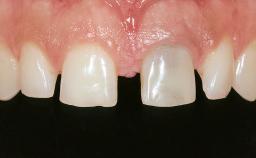

In September 2004, a 38-year-old female patient, a nonsmoker, was referred to our clinic for the replacement of the missing left central maxillary incisor (tooth 21),which had been removed two months before the initial appointment due to a vertical root fracture. The dental patient history revealed that the tooth in question had supported a ceramo-metal crown for more than ten years before the root fracture occurred. Implant therapy (single-tooth replacement) was considered the first therapeutic choice, as the neighboring teeth did not require significant restoration. The patient was in good general health, and her medical history revealed no significant findings.